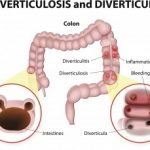

Diverticulitis is a condition characterized by inflamed or ruptured diverticula, which are bulging sacs in the lining of the large intestine. Picking the right foods to eat and steering clear of certain foods to avoid is important for effective management of diverticulitis symptoms.

The risk of developing diverticula is usually higher for people over 40. Diverticula themselves do not cause many problems, but once the condition progresses into diverticulitis – when the sacs get inflamed or infected – it can be quite severe, leading to pain, nausea, and changes to bowels.

Diverticulosis is a condition where pouches develop along the intestines, colon, and even stomach. The risk of diverticulitis increases with age, with over 50 percent of patients being over 60. Generally, the pouches do not cause any issues. The inflammation of the pouches is what is known as diverticulitis. The condition is accompanied by the abdominal pain and infection. Continue reading…

Although at first diverticulitis and colon cancer may present similar symptoms, they are two very different conditions. Diverticulitis is a condition set off by infection or rupture of diverticula, which are bulges forming in the lower part of the large intestine or colon. The risk of developing diverticula is usually higher in people over 40. Diverticula themselves do not cause many problems, but once the condition progresses into diverticulitis, it can be quite severe, leading to pain, nausea, and changes to bowels.

Diverticulitis is a condition onset by infection or rupture of diverticula, which are bulges forming in the lower part of the large intestine or colon. The risk of developing diverticula is usually higher for people over 40. Diverticula themselves do not cause many problems, but once the condition progresses into diverticulitis, it can be quite severe, leading to pain, nausea, and changes to bowels.